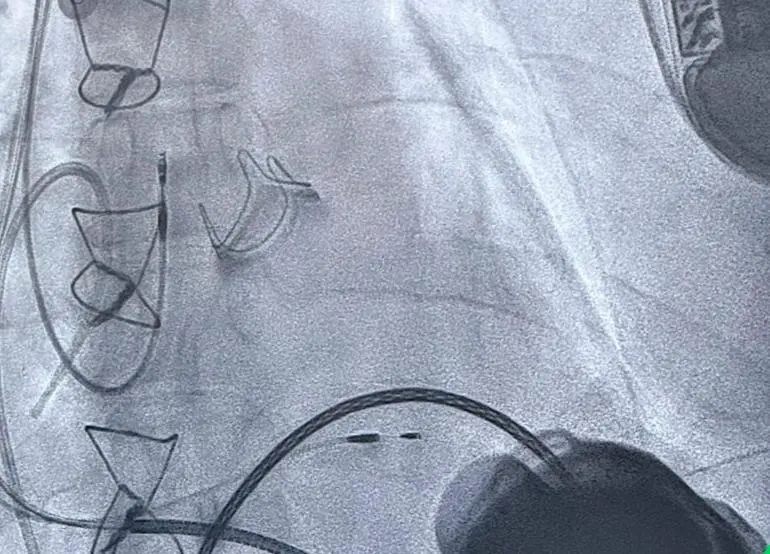

En Medellín se logró un hito médico para Colombia: realizaron dos implantes de corazón artificial en un solo día

El equipo de la Clínica Cardio VID tuvo una agitada y exitosa jornada el pasado 16 de octubre, y logró mejorar la calidad de vida de dos pacientes.

Medellín se acostumbró ser una ciudad de vanguardia para varios procedimientos médicos de alta complejidad. La Clínica Cardio VID marcó un nuevo avance para la medicina cardiovascular al realizar, por primera vez en Colombia, el implante de dos asistencias ventriculares izquierdas de larga duración (Heartmate 3), conocidos también como “corazones artificiales”, en una misma jornada.

Los procedimientos se realizaron el 16 de octubre, en dos pacientes hombres de 48 y 49 años con insuficiencia cardíaca avanzada. Según explicó el doctor Andrés Felipe Barragán, cardiólogo especialista en Insuficiencia Cardíaca Avanzada y Trasplantes, la asistencia ventricular es “una bomba mecánica que ayuda al corazón a impulsar la sangre cuando este ya no tiene la fuerza suficiente para hacerlo por sí mismo”.

La cirugía se realiza mediante una esternotomía medial, es decir, una apertura del esternón para acceder al corazón (lo que se conoce popularmente como cirugía a corazón abierto).

"Se implanta una cánula en la punta del corazón y otra en la aorta ascendente. La bomba succiona la sangre y la impulsa de nuevo hacia el cuerpo, generando un flujo continuo a todos los órganos", detalló Barragán.

Los pacientes que recibieron las asistencias presentaban condiciones que impedían, por el momento, un trasplante de corazón: uno por hipertensión pulmonar y el otro por seguimiento oncológico tras un cáncer renal.

La capacidad técnica, humana y médica para adelantar estos dos procedimientos de alta complejidad en una sola jornada representa una esperanza real para los pacientes con insuficiencia cardíaca avanzada en Colombia.

La Clínica Cardio VID se ratificó como una de las instituciones líderes en procedimientos cardiovasculares de alta complejidad: en Antioquia ya se realizó han cuatro implantes de asistencia ventricular, todos en esta Clínica.